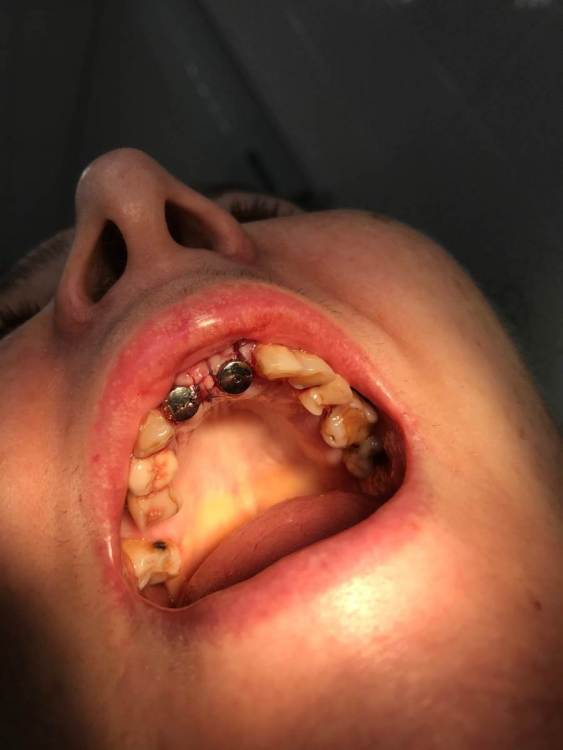

MakovskyAlexandr Опубликовано 8 октября, 2020 Поделиться Опубликовано 8 октября, 2020 Здравствуйте, люди добрые, подскажите пожалуйста.Удалены 2 Корня(21 и 12). Пациентка отказалась от трёх коронок, изъявила желание именно двумя восстановить.Удалены корни - установлены импланты анкилоз А3.5 11 и 14 мм.Выполнена костная пластика , материал ограждён мембраной- все по классике, мембрана фиксирована пинами. Я так понимаю произошло смещение материала( то от гематома, то ли отёк такой). Как быть дальше? Ждать интеграции и подсаживать потом аутотрансплантат?Спасибо огромное. Ссылка на комментарий

MakovskyAlexandr Опубликовано 13 ноября, 2020 Автор Поделиться Опубликовано 13 ноября, 2020 Сколько прошло после имплантации? есть фото? Швы разошлись?Прошёл уже месяц. Нет ничего не разошлось, все зажило, швы давно сняты.Как придёт на приём сфотографирую и скину фото. Ссылка на комментарий

Дмитрий Л. Опубликовано 19 апреля, 2021 Поделиться Опубликовано 19 апреля, 2021 Интересно как решите вопрос протетики. Я бы с техником посоветовался и хотя бы ваксап попросил на 3 ед. Обдумал бы вариант препарирования соседей и покрытия их коронками меньшими по размеру. Если заморочиться. А так вроде норм. Ссылка на комментарий